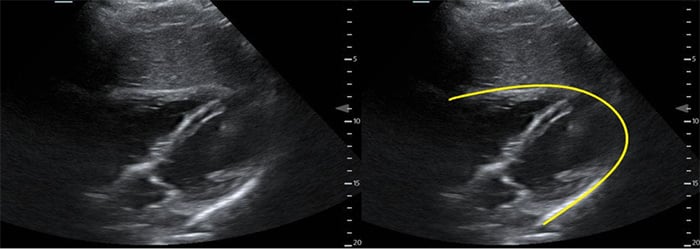

- Ascites (Fig. 6)

- Ascites is a common finding in many disease entities however in the patient with HIV from a TB endemic area, it is highly suggestive of TB.

- With or without fibrinous debris: OR 2.221

- Without fibrinous stranding: PPV= 73% NPV = 33%18

- With fibrinous stranding: PPV = 86% NPV= 41%18

Figure 7. Fibrinous ascites in pelvis sagittal view

Figure 8. RUQ free fluid with fibrinous stranding and hyperechoic liver lesions